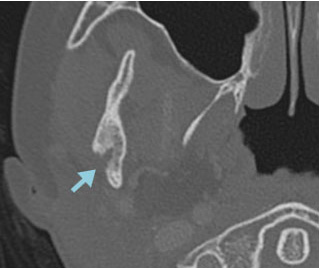

右下顎骨にLCHの骨再発をきたした。HU内服治療を開始後、溶骨部分の順調な修復が認められた。

CT 骨条件

4か月後 * 患者さんから許可を得て掲載しています。